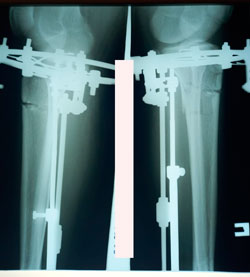

Исходник - 35 лет.

Дата операции - 15.01.2021

Анталия